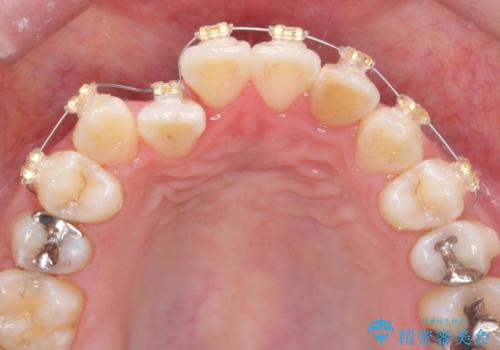

引っ込んだ前歯を並べたい マウスピースと部分ワイヤーのコンビネーション矯正

- インビザライン +部分ワイヤー矯正

まずマウスピース矯正インビザラインシステムで、引っ込んだ歯が並ぶためのスペースを作ったのち、部分ワイヤー矯正を行い短期間での配列を計画します。

マウスピース・ワイヤーそれぞれの長所をうまく活かすことで治療期間の短縮が可能となります。

このように前歯の部分ワイヤーは引っ込んでしまった前歯や がたつきを素早く改善することができます。